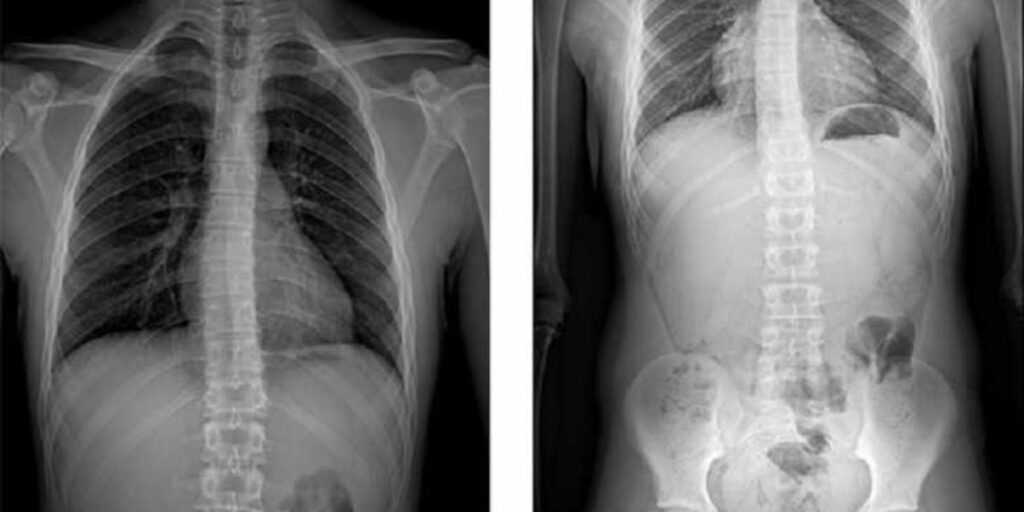

L’Esame RX Rachide Completo è una radiografia specifica che cattura immagini dei segmenti cervicale, toracico e lombare della colonna vertebrale. Presso il Poliambulatorio S-Medical Group di Sora, questo esame viene eseguito con strumentazione all’avanguardia per garantire una diagnosi accurata e precisa. Le immagini radiografiche ottenute permettono ai nostri specialisti di analizzare l’intera colonna vertebrale, evidenziando eventuali anomalie o problematiche.

Le immagini radiografiche fornite dall’Esame RX Rachide Completo consentono di valutare la salute della struttura ossea della colonna vertebrale. È possibile identificare:

• Fratture vertebrali.

• Disallineamenti o deformità della colonna.

• Ernie del disco.

• Problemi articolari come l’osteoartrite.

• Anomalie congenite o acquisiti nel tempo.